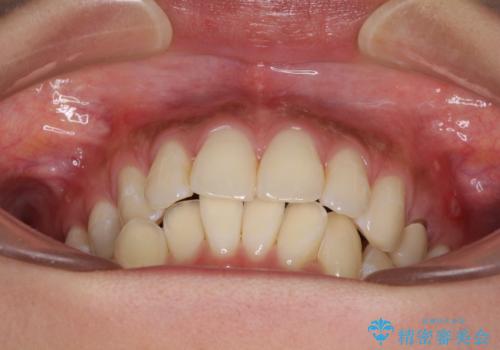

八重歯の再矯正 インビザラインでストレスなく矯正治療

- 学生の頃に矯正治療を行ったものの、保定を怠けてしまったことによる後戻りを気にして来院された患者様です。

下顎の八重歯が上顎歯列に収まる過程で咬みにくさがありましたが、最終的には、咬み合わせも安定し、きれいに歯列を整えることができました。